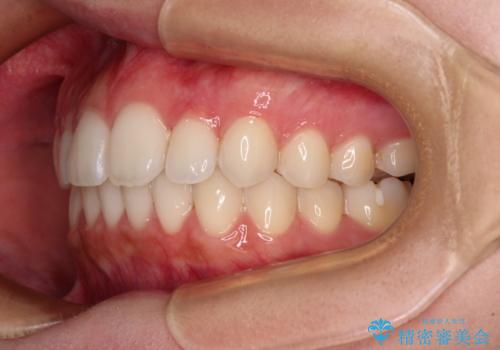

【モニター】前歯のクロスバイトをインビザラインで治療

- 前歯のデコボコとクロスバイトを気にして来院された患者様です。

上顎側切歯(上の真ん中から2番目の歯)が舌側転位している場合、インビザラインでは仕上げきれないことが多く、更には無理して動かそうとすると歯髄壊死を起こすリスクが高いと言われています。

今回は、ワイヤー装置を併用することなく、インビザライン単体で矯正治療を行うこととしました。

インビザライン特有の、奥歯の咬み合わせの問題もなく、しっかりと歯列を改善することができました。

舌側転位している上顎側切歯(内側に引っ込んでいる真ん中から2番目の歯)は、インビザラインが最も移動を苦手とする歯であり、これ以上の改善を望まれる場合にはワイヤー矯正、あるいはワイヤー矯正の併用をお勧めいたします。